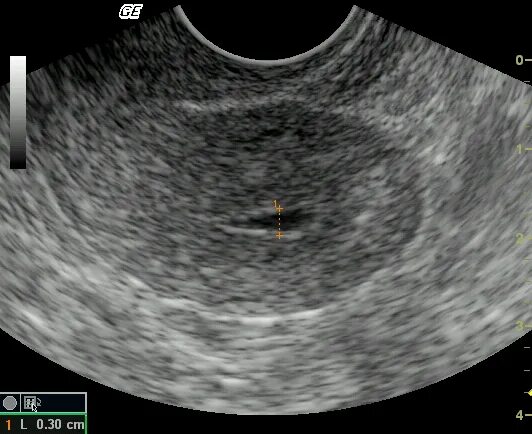

Эндометрий 9 мм